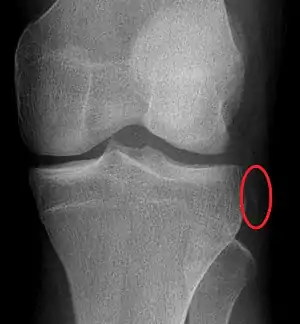

The Segond fracture is a type of avulsion fracture (soft tissue structures pulling off fragments of their bony attachment) from the lateral tibial plateau of the knee, immediately below the articular surface of the tibia (see photo).

| Segond fracture of left knee | |

Segond and reverse Segond fractures are characterized by a small avulsion,[5] or "chip", fragment of characteristic size that is best seen on plain radiography in the anterior-posterior plane. The avulsed fragment of bone may be very difficult to see on the plain x-ray exam, and may be better seen on computed tomography. MRI may be useful for visualization of the associated bone marrow edema of the underlying tibial plateau on fat-saturated T2W and STIR images, as well as the associated findings of ligamentous and/or meniscal injury.